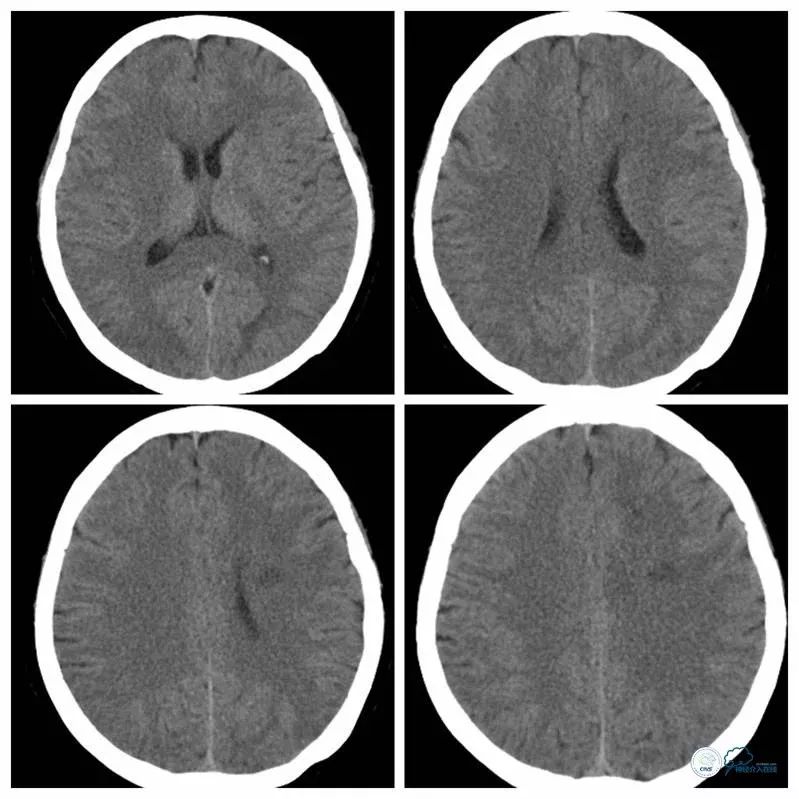

术前CT:左侧脑室旁梗死(图1)。

图1